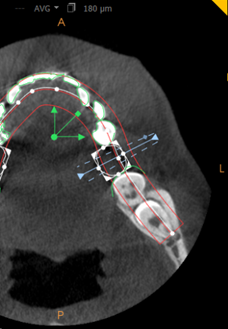

The position of an imported crown can be adjusted manually in the Curve tab, using the object editing tools displayed in the following view screens:

Axial Slice View Screen ![]()

Reconstructed Panoramic View Screen ![]()

Oblique Coronal Slice View Screen (Cross-section) ![]()